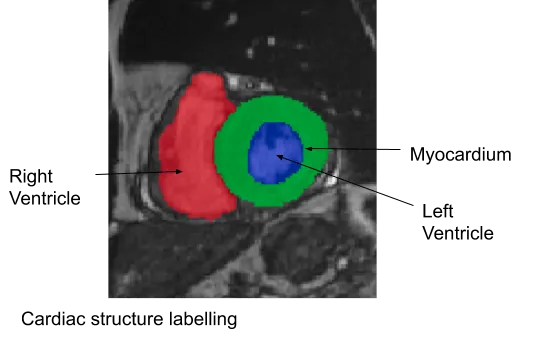

One of the complex and challenging diagnosis tasks involves cardiac cine Magnetic Resonance Imaging (MRI). Cardiac cine Magnetic Resonance Imaging (MRI) is primarily used for the assessment of cardiac function and diagnosis of Cardiovascular diseases (CVDs). Cardiac MRI is considered the most accurate method for the estimation of clinical parameters such as ejection fraction, ventricular volumes, stroke volume and myocardial mass. Cardiac cine MRI consists of images of the cross sections of the heart (entire heart can be covered) acquired at different time points during the cardiac cycle including end systole and end diastole. The diagnosis tasks consists of image segmentation to segment the left ventricle and derive quantitative measures to diagnose specific heart conditions.

We developed a deep learning based framework for cardiac segmentation which incorporated cardiac structures segmentation and cardiac disease diagnosis. The figure below illustrates the pipeline. The pipeline involved:

- FCN for cardiac structures segmentation: A typical semantic segmentation architecture comprises a down-sampling path (contracting) and an up-sampling path (expanding).

By following these steps in framework and network design, we achieved almost state-of-the-art performance on multiple cardiac segmentation datasets namely- (i) On STACOM ACDC-2017 challenge test set for segmentation task achieved a mean dice score of 0.94, 0.91 and 0.89 for the left ventricle, right ventricle and myocardium respectively and for automated cardiac disease diagnosis the accuracy was 100%, (ii) On STACOM LV-2011 test set the approach achieved 0.74 Jaccard index for myocardium segmentation. On the Kaggle challenge test set, the approach gave a continuous ranked probability score (CRPS) of 0.0127 for left ventricular volume estimation.